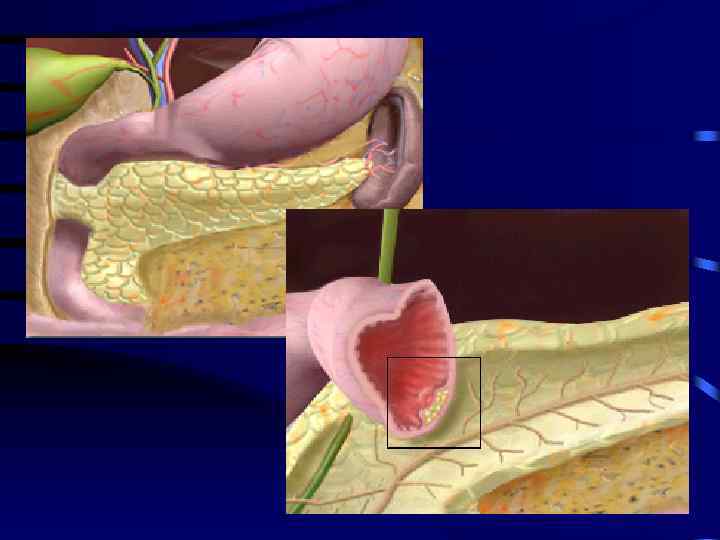

УЗИ диагностика кольцевидной поджелудочной железы: что важно знать